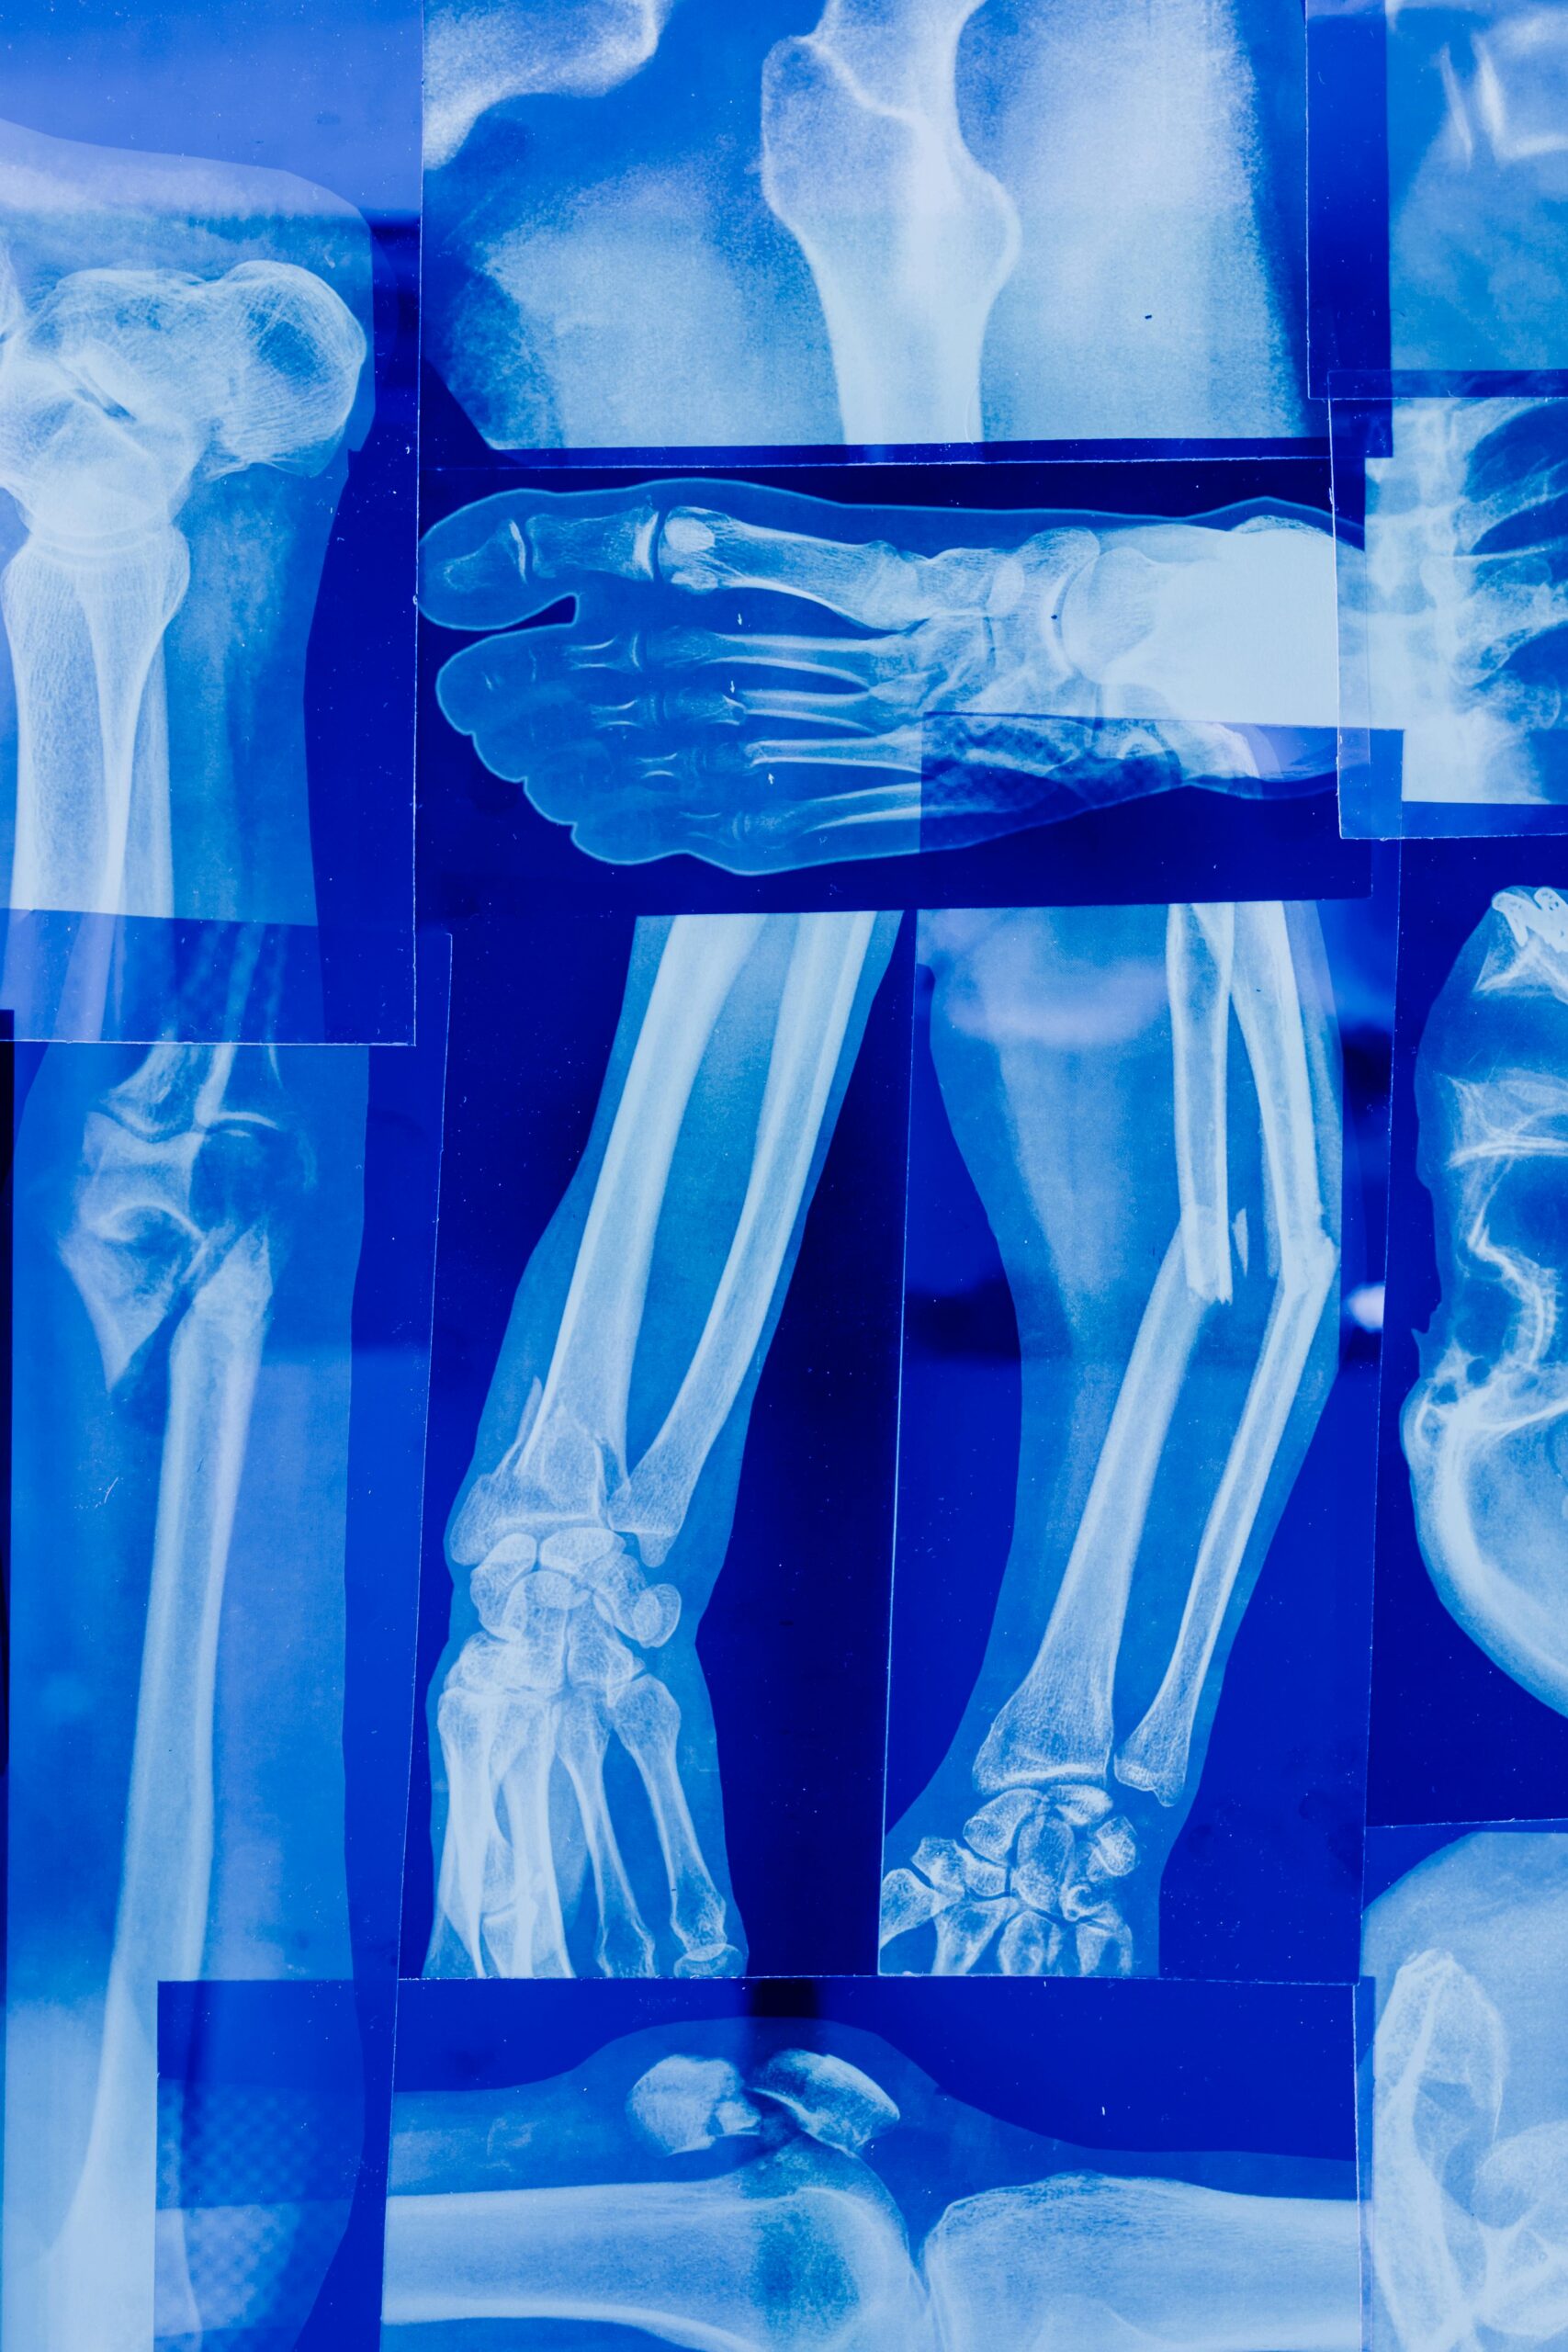

🩻 الأشعة السينية (X-Ray): أداة أساسية للتشخيص الطبي

الأشعة السينية (X-Ray) هي فحص تصويري سريع يستخدم الأشعة لتكوين صور للعظام والأعضاء الداخلية، مما يساعد الأطباء على تشخيص الإصابات والأمراض بدقة وسرعة.

🩺 استخدامات الأشعة السينية

- تشخيص الكسور والإصابات العظمية:

تحديد مكان وكثافة الكسور وتشخيص مشاكل المفاصل. - أمراض الرئة والجهاز التنفسي: